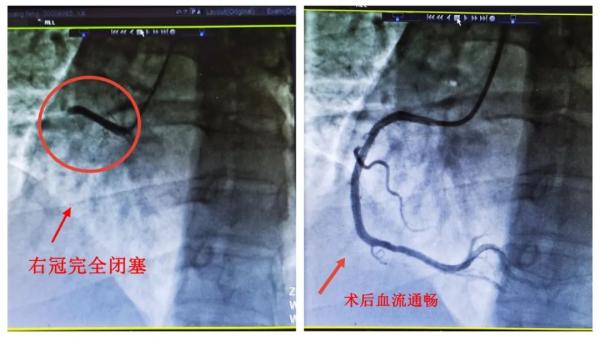

冠脉造影提示王大哥右冠近段完全闭塞,必须马上开通血管。刘喆团队仅用时5分钟即为患者开通闭塞的血管并植入支架一枚。术后,患者胸痛不适症状随即缓解。